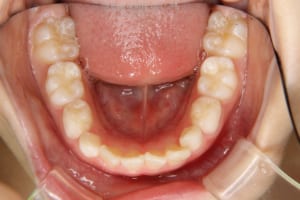

歯列弓の狭窄を伴う上顎前突の小学生男子の治療例

治療前

治療後

| 主訴 | 上の前歯が出ている 上の前歯が斜めに生えている |

| 治療内容 | 子どもの矯正治療を行いました。 |

| 使用した装置 | 上下に緩徐拡大装置 トランスパラタルアーチ リンガルアーチ ヘッドギアー 部分的なマルチブラケット装置 筋機能訓練(MFT)は行っていません。 |